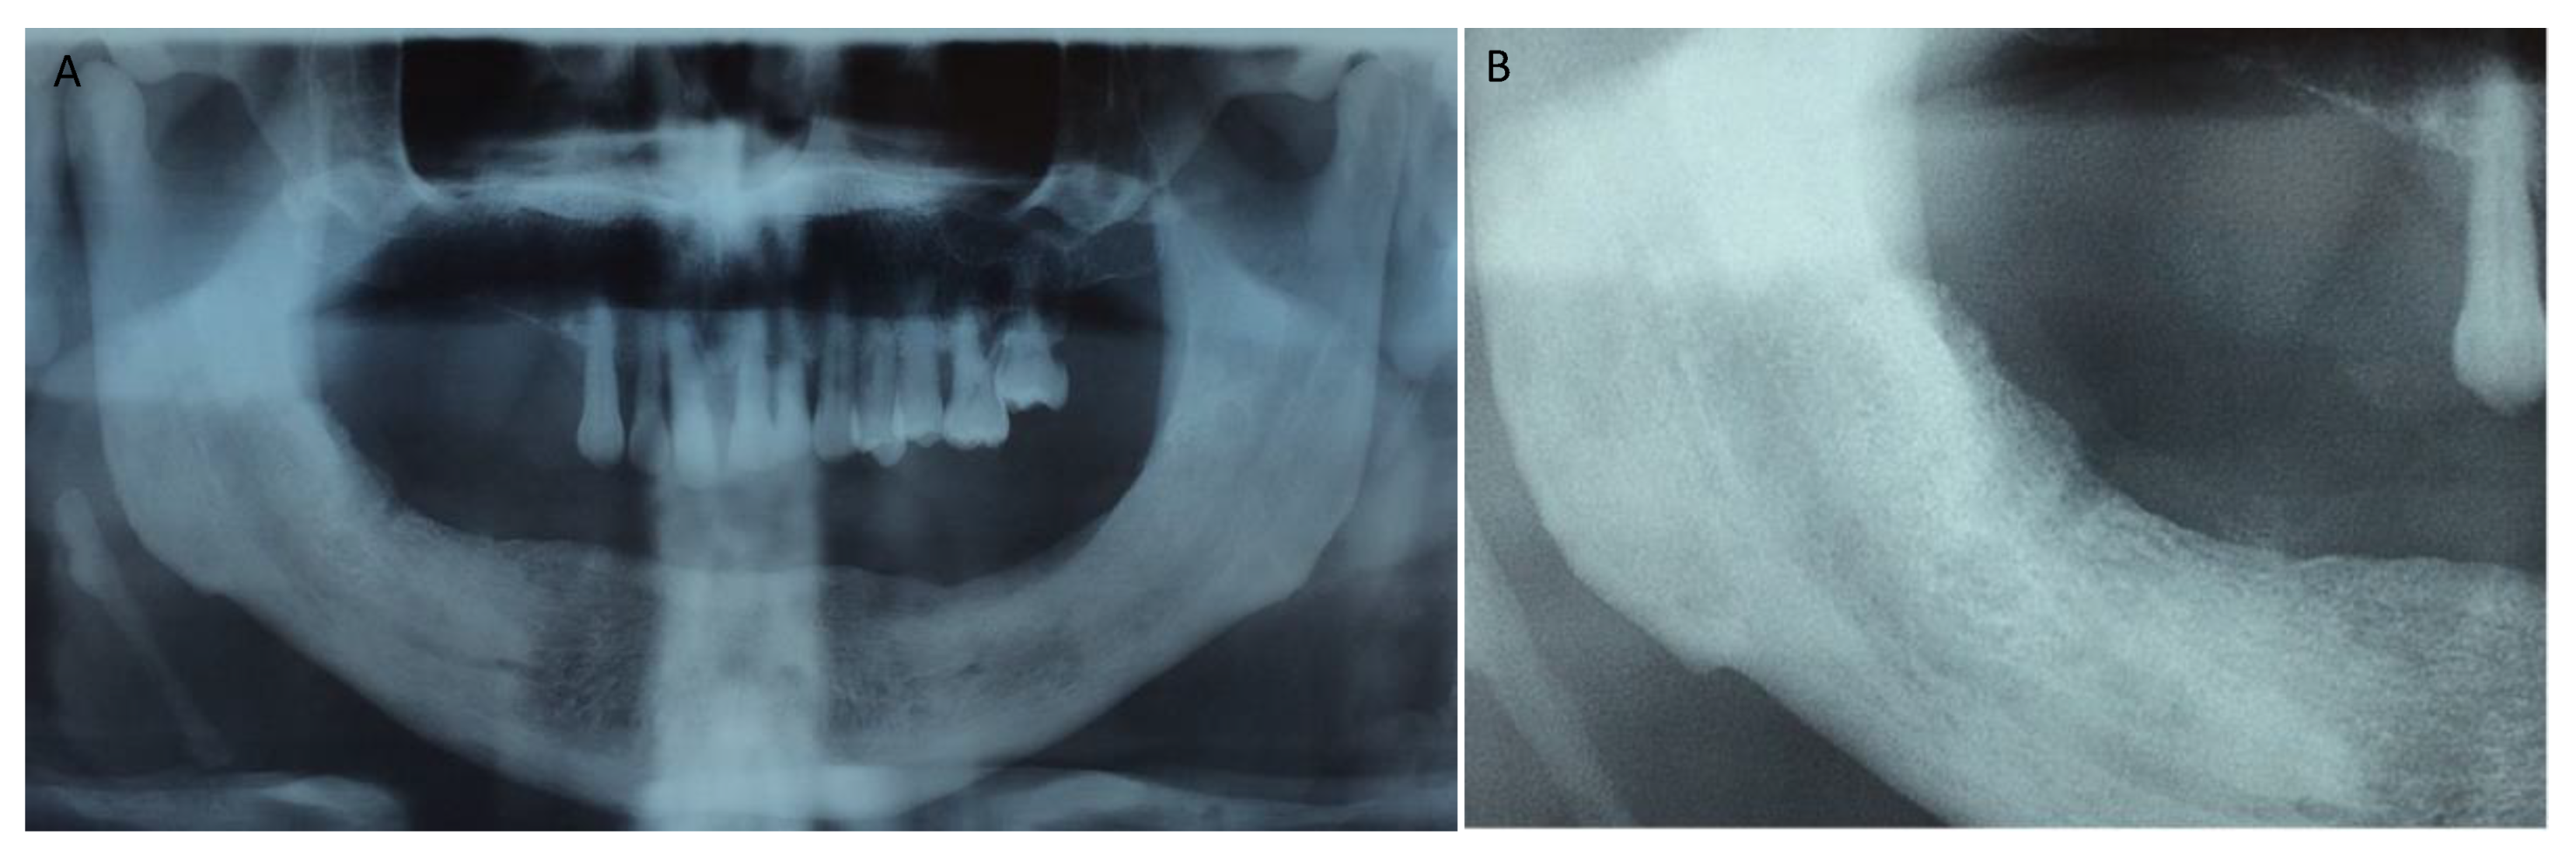

Figure 1, Figure 2, Figure 3, Figure 4, Figure 5, Figure 6 and Figure 7 show the progress of treatment in one of the patients of the test group. In Figure 3 reduction of the medullar space is visible, that may create a chronic ischemic area susceptible to necrosis.

Figure 2.

Pre-operative orthopantomography of the same MRONJ patient showing bilateral defect; (A) shows the panoramic view; (B) shows more detail of the right side of the mandible.

Figure 3.

Pre-operative CBCT of the MRONJ patient, showing a reduction in the medullar space.